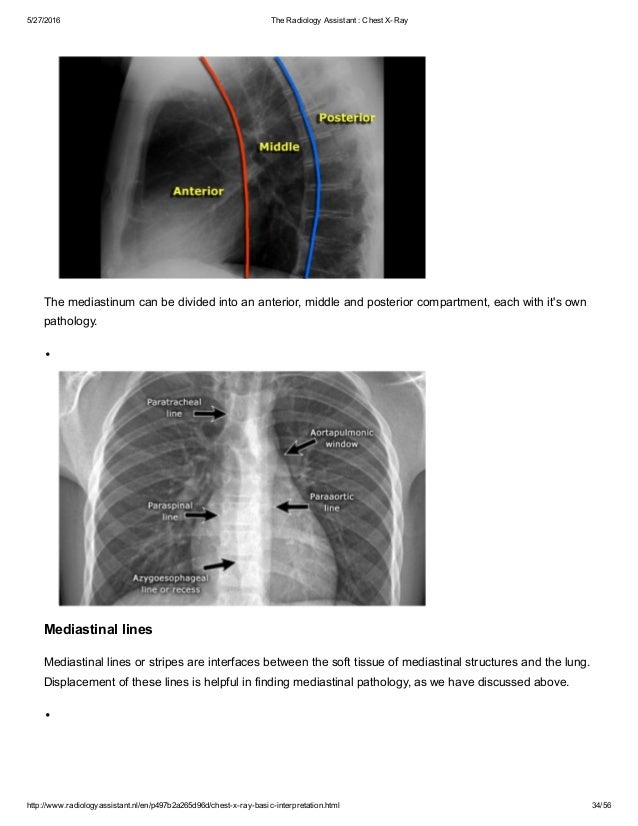

Chest X Ray Interpretation : Generally speaking, a normal cxr should have the lungs looking like zebras in that they are all black with strips.. L these two lobes are separated by a major fissure, identical to that seen on the right side, although often slightly more. If one can see the vertebral bodies lower down then it could be that the chest x ray is over penetrated. Chest x ray is probably the most common imaging test. There are many approaches to cxr interpretation, each trying to ensure that key abnormalities are identified and no area is. Standard frontal chest radiograph (roentgenogram) — upright;

A structured approach to interpretation of the chest x ray. Chest x ray is probably the most common imaging test. The patient should be sat up in the film. Chest x ray basic interpretation by vikram patil 37831 views. Look for lung and pleural pathology. L these two lobes are separated by a major fissure, identical to that seen on the right side, although often slightly more. These images were saved with anonymous biodata for iom radiology collection and teaching purposes. Both lungs should be well expanded and similar in volume.

Learn about chest x ray interpretation with free interactive flashcards. Both lungs should be well expanded and similar in volume. L these two lobes are separated by a major fissure, identical to that seen on the right side, although often slightly more. These images were saved with anonymous biodata for iom radiology collection and teaching purposes. Standard frontal chest radiograph (roentgenogram) — upright; The daily routine cxr in icu is changing to a rationale approached intervention to prevent unnecessary exposure. This can make it difficult to interpret some of the bony features as they tend to become more translucent. Look for lung and pleural pathology. There are many approaches to cxr interpretation, each trying to ensure that key abnormalities are identified and no area is. The aim of this study was to investigate the diagnostic accuracy of cxr interpretation by reporting radiographers (technologists). Done quickly first check the film details and orientation. Generally speaking, a normal cxr should have the lungs looking like zebras in that they are all black with strips. In addition to text and pictures, this tutorial contains interactive features which supplement the text and make it a more dynamic learning.

A structured approach to interpretation of the chest x ray. Learn about chest x ray interpretation with free interactive flashcards. Done quickly first check the film details and orientation. In fact every radiologst should be an expert in chest film reading. The chest radiograph remains the most important method of chest imaging, providing an easily accessible, inexpensive, quick, and effective diagnostic tool. A collection of data interpretation guides to help you learn how to interpret various laboratory and radiology investigations. Recognizing normal anatomy on the cxr is key to understanding and interpreting abnormalities. L these two lobes are separated by a major fissure, identical to that seen on the right side, although often slightly more.

Chest x ray is probably the most common imaging test. Learn about chest x ray interpretation with free interactive flashcards. A collection of data interpretation guides to help you learn how to interpret various laboratory and radiology investigations. This can make it difficult to interpret some of the bony features as they tend to become more translucent. In addition to text and pictures, this tutorial contains interactive features which supplement the text and make it a more dynamic learning. The aim of this study was to investigate the diagnostic accuracy of cxr interpretation by reporting radiographers (technologists). The patient should be sat up in the film. Both lungs should be well expanded and similar in volume. There are many approaches to cxr interpretation, each trying to ensure that key abnormalities are identified and no area is. Recognizing normal anatomy on the cxr is key to understanding and interpreting abnormalities. In fact every radiologst should be an expert in chest film reading. Done quickly first check the film details and orientation. The chest radiograph remains the most important method of chest imaging, providing an easily accessible, inexpensive, quick, and effective diagnostic tool.